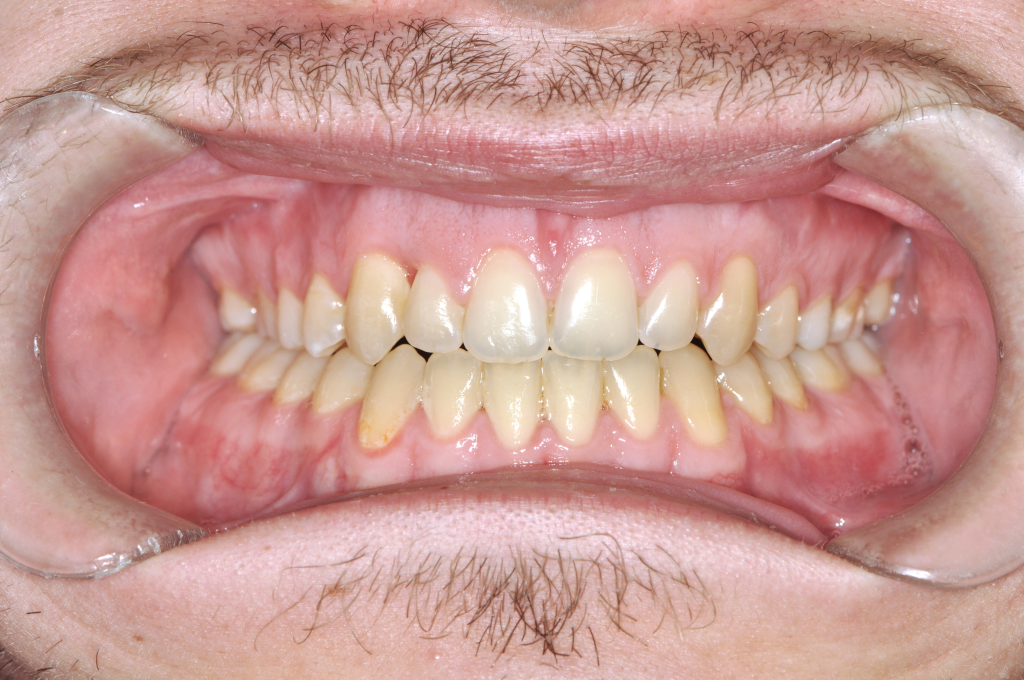

Előtte fogsor - Ínymosoly műtéti megoldása​

Utána fogsor - Ínymosoly műtéti megoldása​

Az ínymosoly ebben az esetben nem pusztán esztétikai kérdés volt.

A felső állcsont függőleges túlnövekedése és az alsó állkapocs helyzete együtt bontotta meg az arányokat.

A kezelést fogszabályozással készítettük elő, majd kétállcsontos állcsontműtétet végeztünk.

A felső állcsont pozíciójának módosításával csökkent az ínyláthatóság,

az alsó állkapocs korrekciója pedig stabil harapást eredményezett.

Eredmény: kevesebb íny, harmonikusabb arcprofil, hosszú távon stabil funkció..